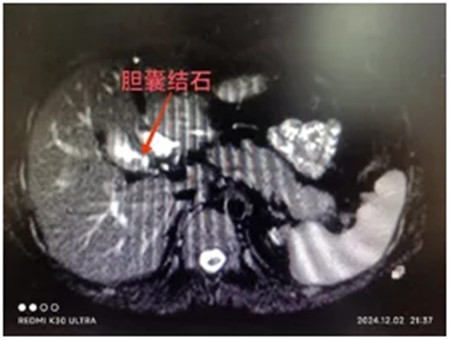

24岁的李同学(化名)进食油腻食物后突发右上腹疼痛,伴恶心、呕吐,自行口服止痛药,未见明显好转,忍不了的李同学来到郑州大学第五附属医院肝胆胰腺外科慕名找到陈艳军主任,经过细致的问诊和查体,并进一步完善血常规、肝肾功能、核磁共振(MRCP)等化验检查,原来是胆囊结石在作祟。